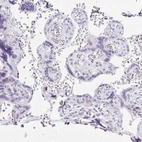

Immunohistochemistry analysis in human fallopian tube and placenta tissues using Anti-C20orf85 antibody. Corresponding C20orf85 RNA-seq data are presented for the same tissues.